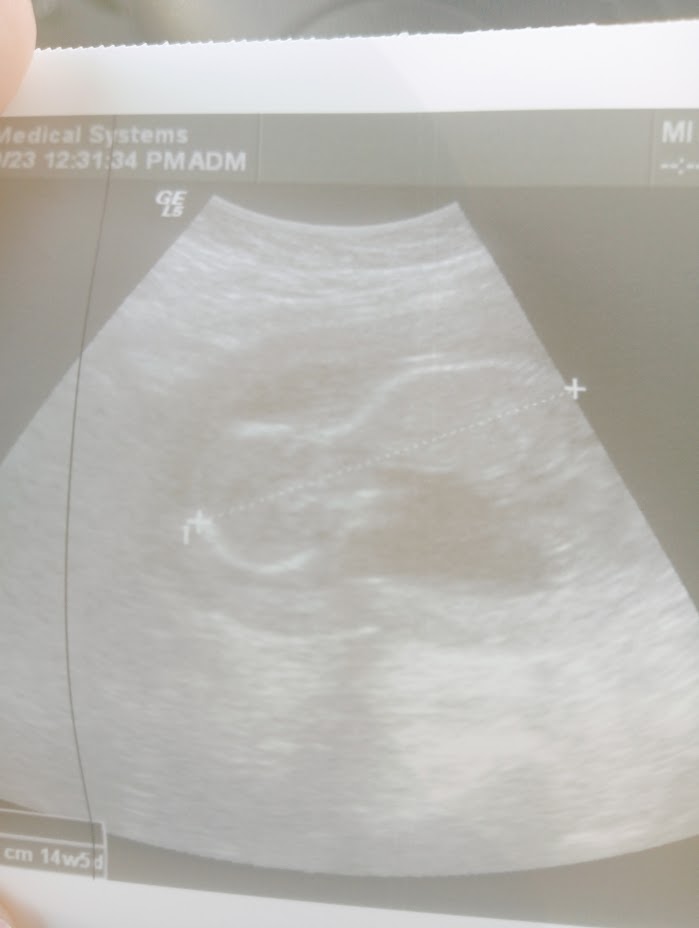

ostatnie badania mialam 1,5 miesiaca temu, bo lekarz mial urlop, po dzisiejszej wizycie znow nie mam zleconych zadnych badan nawet moczu. kolejna wizyta za miesiac. lekarz nic praktycznie nie zmierzyl, tylko dlugosc dzidziusia, powiedzial ze serduszko bije i pokazal jak maluch sie rusza.mam synka ktory mial wrodzona wade, mimo tego lekarz nie wspomnial o prenatalnych (choc i tak byloby za pozno bo dzis wyszedl 14+5 tygodnia).lekarzowi dzis przyblizyl sie termin z usg prenatalnym, bo wczesniej dziecko wychodzilo u niego o jeszcze 2 tyg mniejsze, jednak zaufalam lekarzowi u ktorego bylam prywatnie i juz 2 tygodnie jestem po badaniach prenatalnych, lekarz nfz nie wyliczyl jeszcze terminu porodu (moze na przyszlych badaniach i moze wtedy tez plec). jesli mialabym polegac na lekarzu nfz to chyba bym zwariowala jesli cala ciaze bym miala nie wiedziec co dzieje sie z dzieckiem, chyba koncze przygode z lekarzem na NFZ